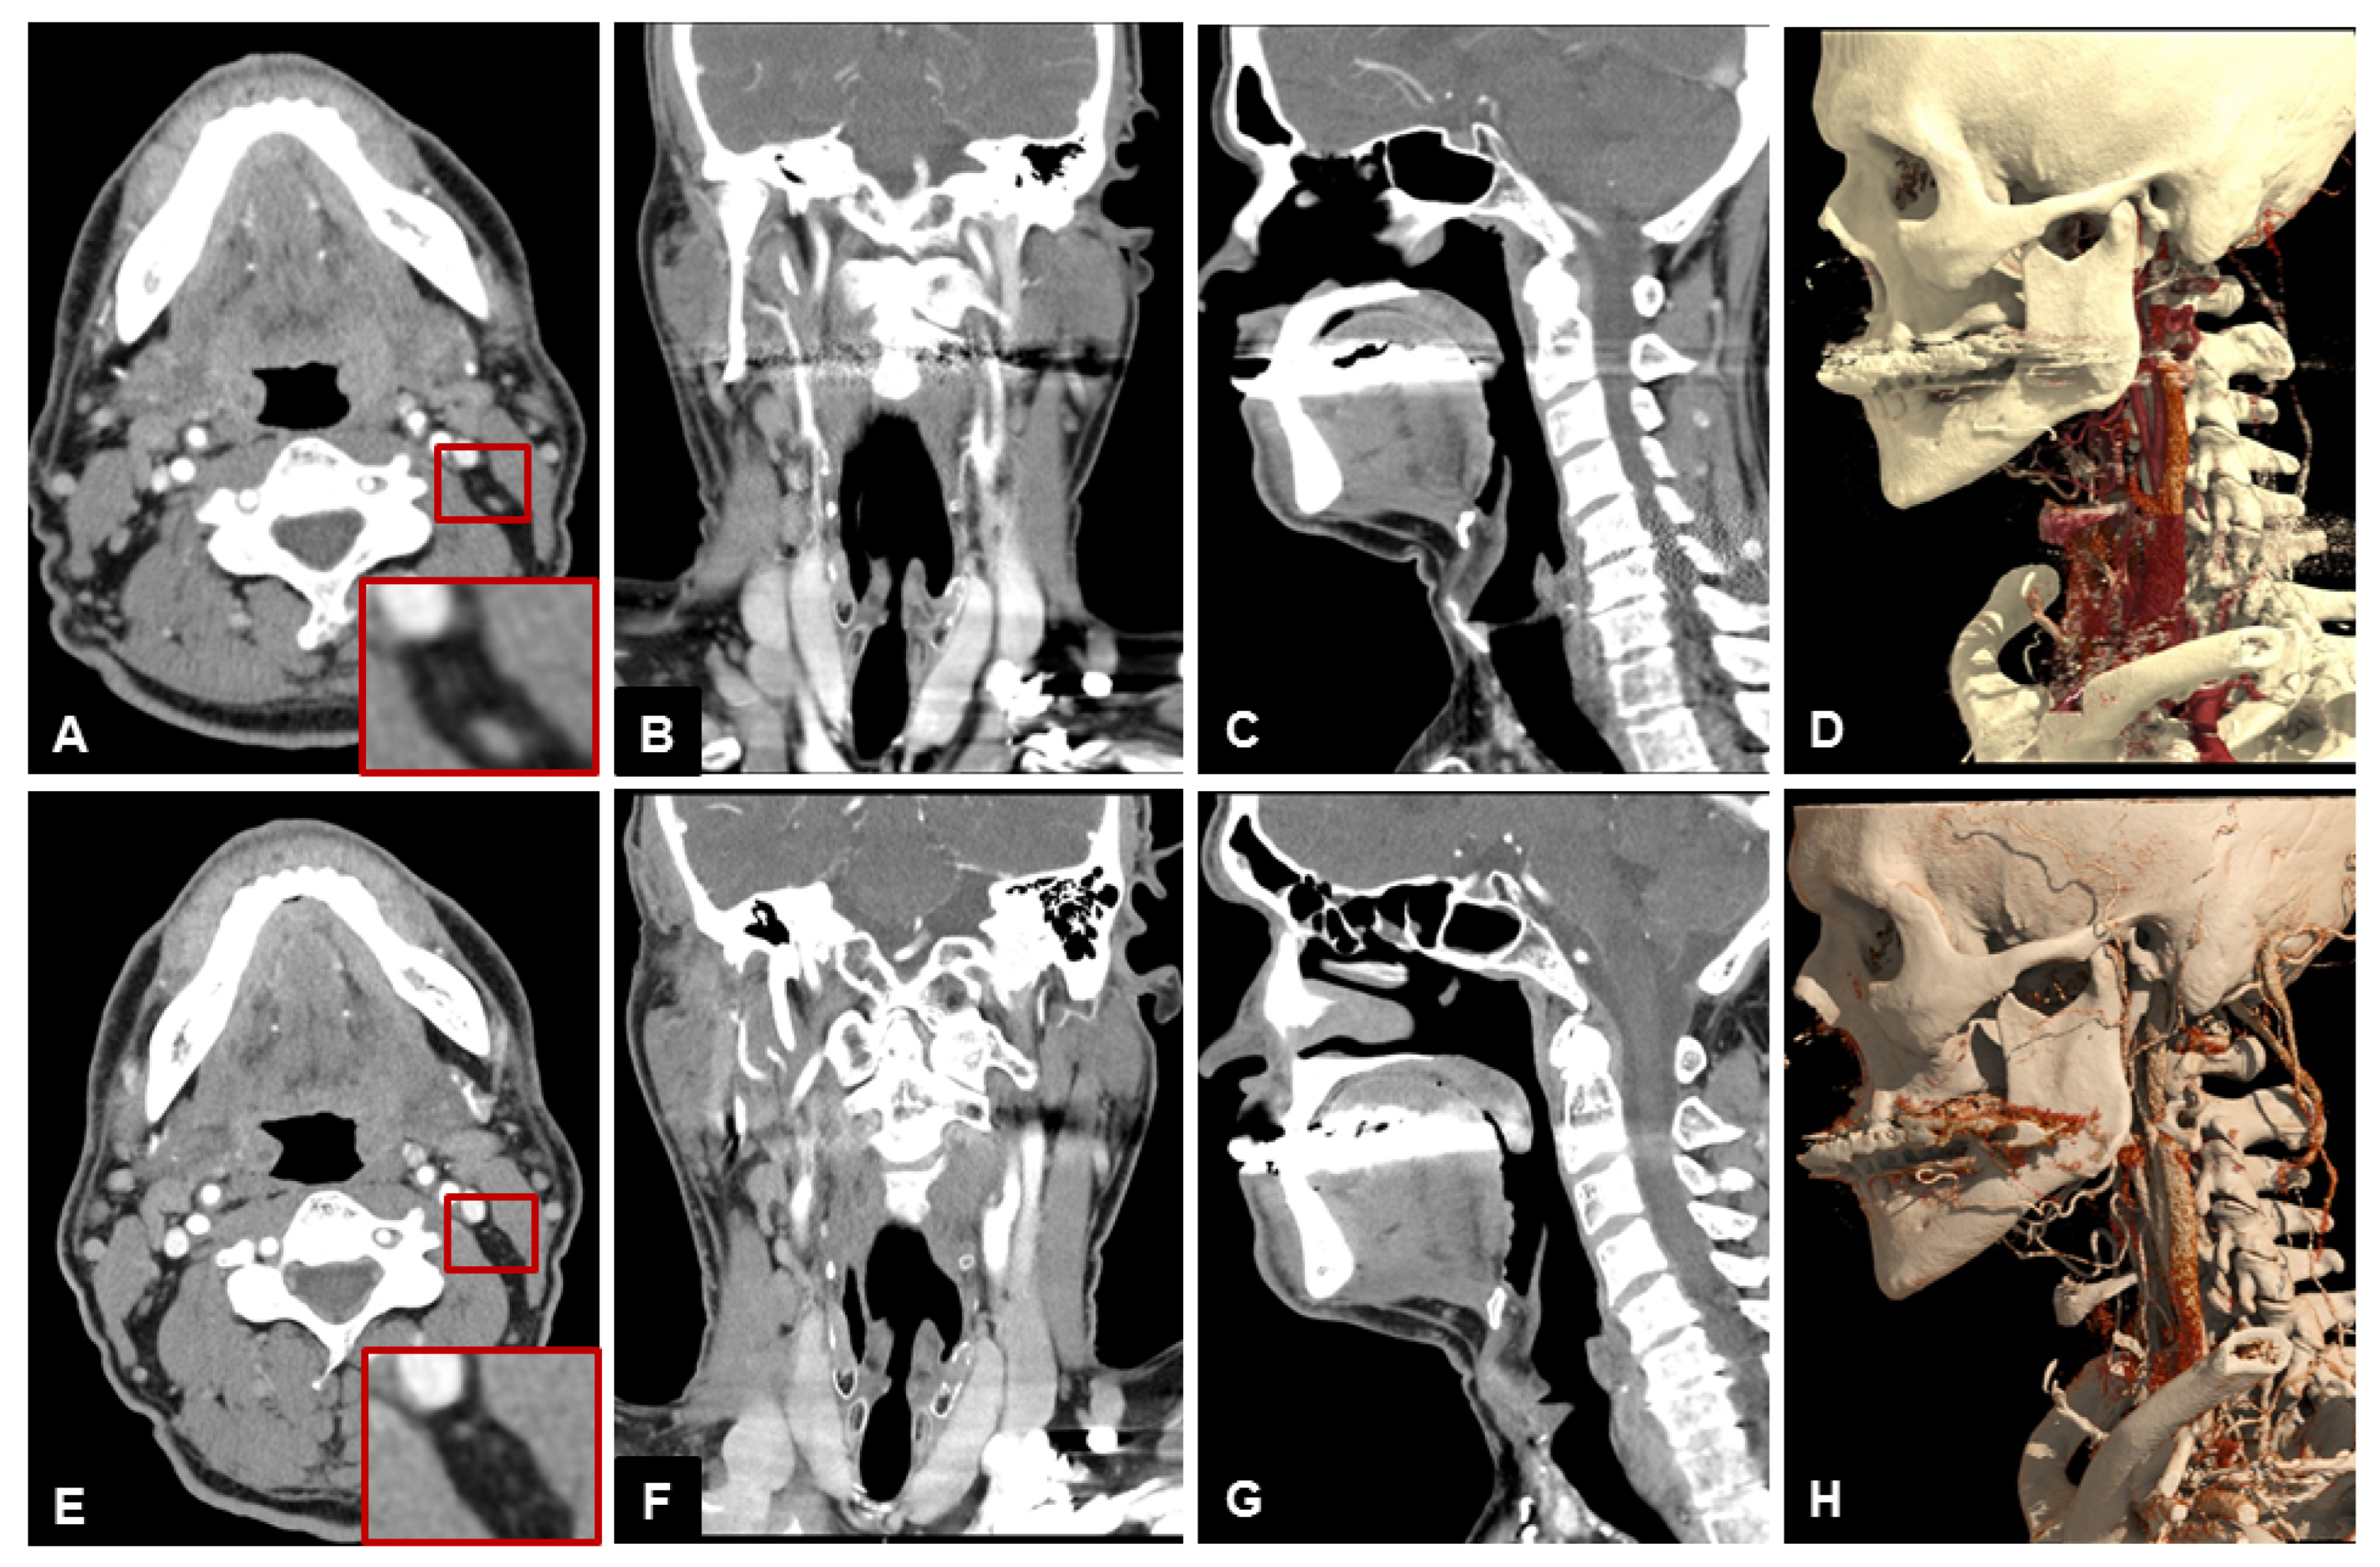

3.2. Subjective Image Quality